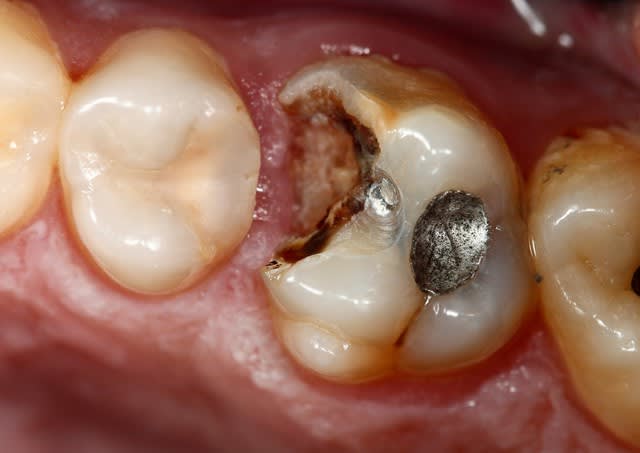

Ici, je fais l'endo en essayant de garder ce que je peux de la dent...

Ensuite a la fin de l'endo, c'est propre, j'ai un accès étanche, j'en profite pour coller et remonter la limite. C'est le meilleur moment pour le faire, non ? ... Et surement le meilleur moyen d'avoir une étanchéité sur la zone faible de cette dent, sa limite proximale infra gingival.

Ensuite le cas parait plus simple bien sur Marc ;) mais en fait tout découle de la prise de décision initiale de préserver et coller...

Onlay Emax. Tout est dans l'émail a part la limite mesiale, le risque de carie est plus faible, le risque de contamination de l'endodonte plus faible aussi...

Mécaniquement ça me parait un meilleur choix que la couronne avec inlay core...